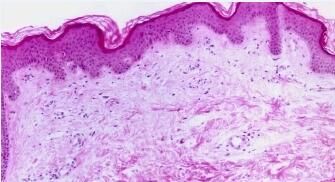

剥脱性皮炎型药疹(drug eruption,exfoliativc dcrmatitis typc) 本型为重型药疹,亦称红皮病型(erythroderma typc)药疹。

剥脱性皮炎型药疹病因:较常见的药物因素是链霉素、磺胺、抗疟药、苯妥英、青霉素及卡马西平等。

多由发疹型药疹演变而来,特别在未停用致敏药物的情况下更易发生。也可由发生于身体皱褶处的红斑、渗出开始,逐渐泛发形成。